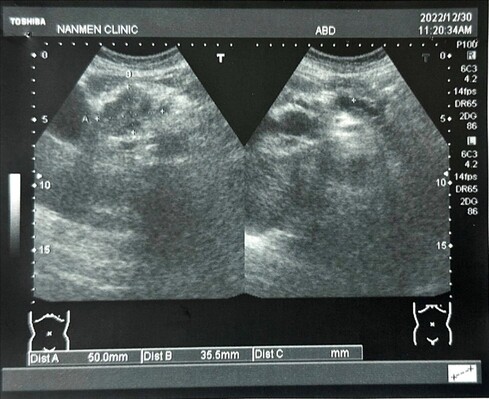

一位60幾歲女士,近日因上腹不適安排腹部超音波檢查。

於超音波下,發現上腹有一個不規則腫瘤位於胰臟的頭部

高度懷疑是源於胰臟的腫瘤,轉診至醫院後,確定為胰臟癌。